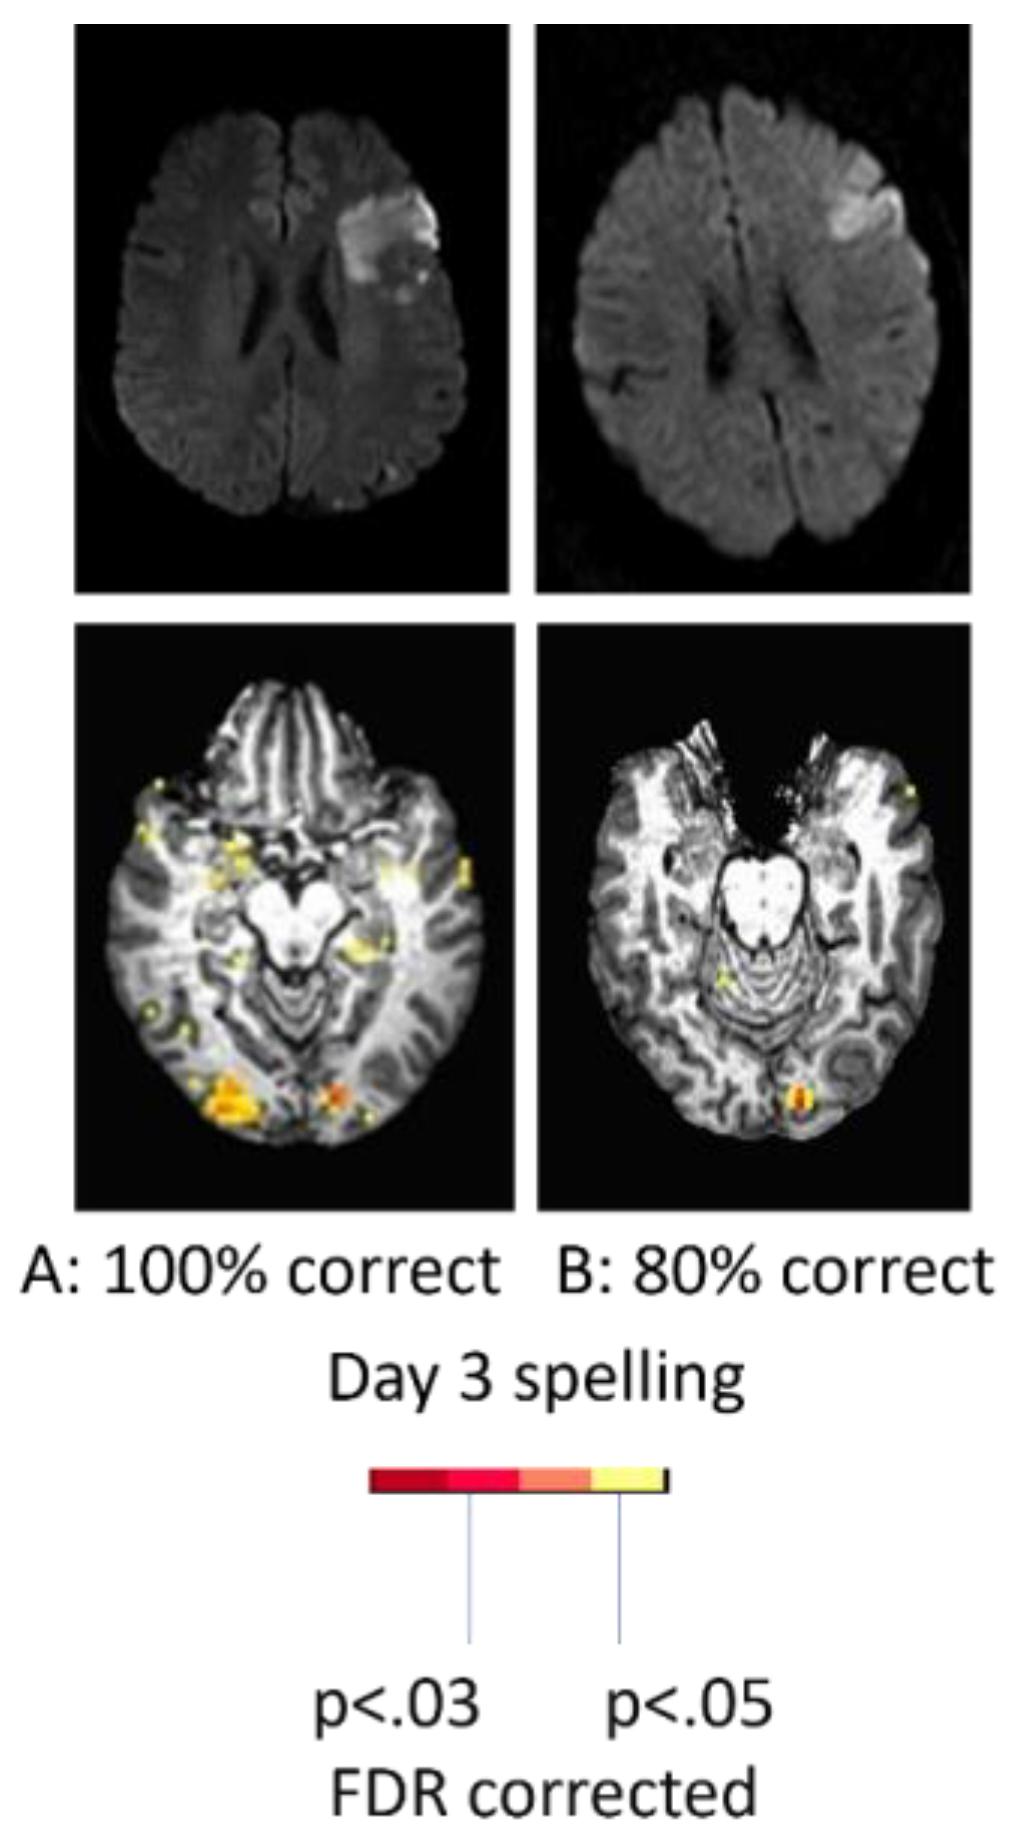

With regard to the effect of accuracy of performance, two women of similar ages with very similar infarcts involving left posterior inferior frontal cortex (“Broca’s area”), showed quite different patterns of activation during a spelling task (identifying the missing letter in a word vs identifying the letter with a different case in a word) at Day 3. While the participant with 100% accuracy showed bilateral (right more than left) activation in areas similar to controls, the participant with 80% accuracy showed only left hemisphere activation as shown in Figure 2. These data raise doubts that right hemisphere homologous activation is detrimental, since it was associated with flawless performance [27].

Figure 2. Top. Diffusion-weighted images showing acute infarct in similar areas of left IFG. Lower panel. Bilateral occipital activation and temporal activation during picture naming in the woman with accurate naming (left); only left occipital activation during picture naming in the woman with impaired naming.